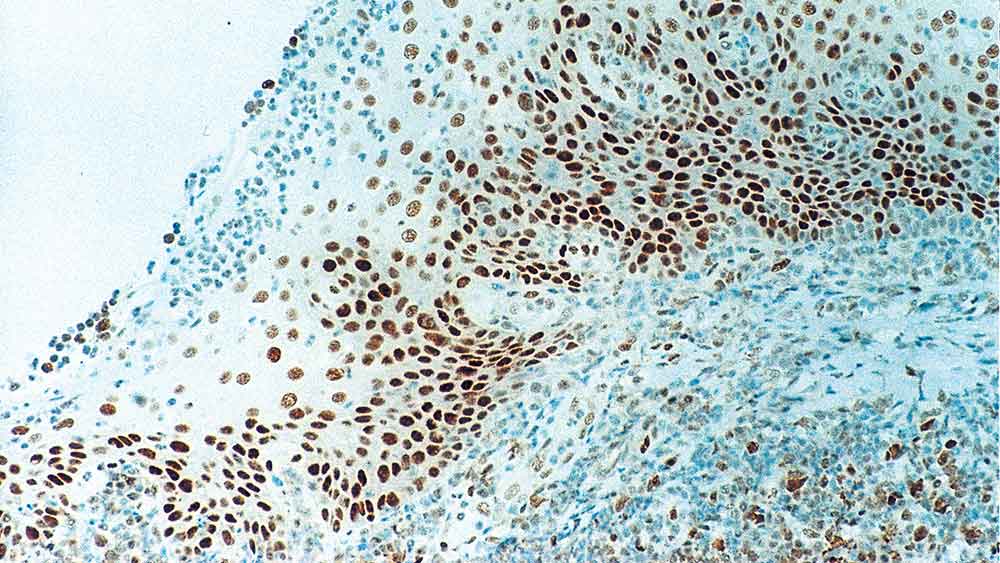

Human tonsil: immunohistochemical staining for Retinoblastoma Gene Protein. Note intense nuclear staining of epithelial cells. Retinoblastoma Gene Protein: clone 13A10

Retinoblastoma (Rb) is a rare tumor of the retina associated with mutations of chromosome 13. The nuclear phosphoprotein encoded by the Rb tumor suppressor gene is present in many cells and may indirectly regulate cell growth by activating the transcription factor ATF-2. Activation of ATF-2 initiates expression of TGF-beta2, which in turn inhibits transcription of genes affecting cell growth. Bilateral mutation of the Rb gene may potentially play a role in the development of a number of malignant tumors.

Retinoblastoma Gene Protein is recommended for the detection of specific antigens of interest in normal and neoplastic tissues, as an adjunct to conventional histopathology using non-immunologic histochemical stains.